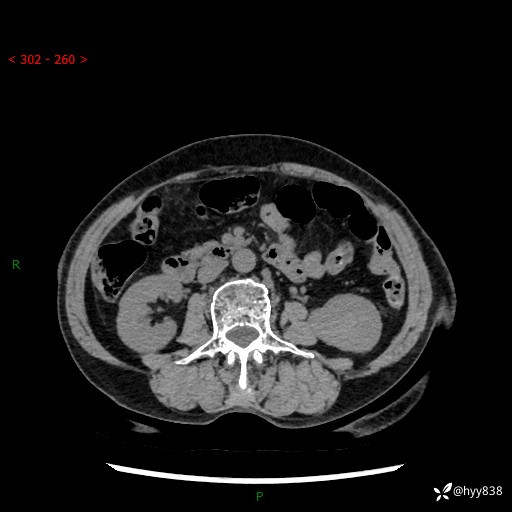

72岁/女,检查发现左肾占位1天。为了满足诊断,常规四期后,又加了延迟期-结果公布~

【患者信息】:72岁/女

【主诉】:检查发现左肾占位1天

【现病史及既往史】:患者于1天前检查发现左肾占位,无畏寒发热,无咳嗽咳痰,无腰腹部疼痛不适,无肉眼血尿、无尿频尿急症状,起病来,患者未行特殊治疗,为求进一步诊治,门诊以"左肾占位"收治入院。 发病来患者精神、饮食、睡眠良好,小便如上,大便正常,体重无明显变化。

【检查】:肾脏CT平扫+增强